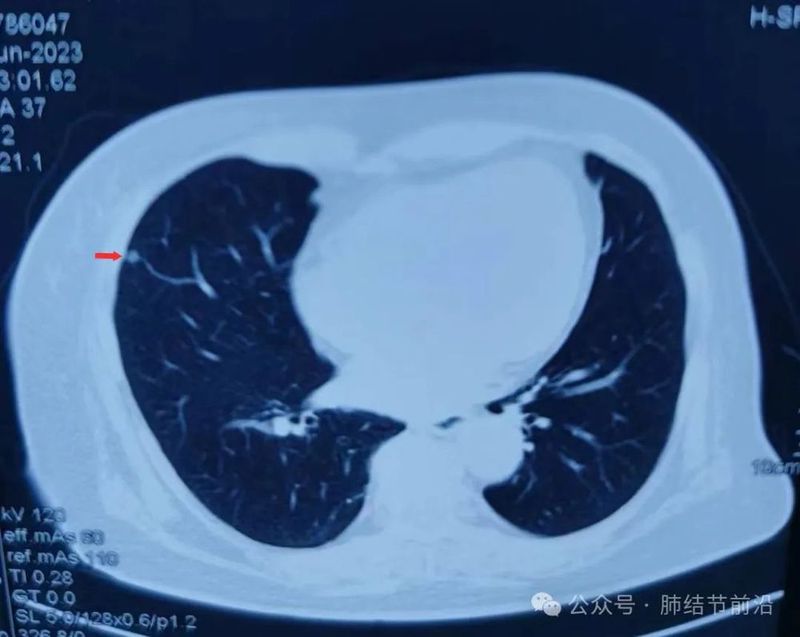

中年女性,偶发肺结节来诊,就诊国内某顶级医院CT,报告显示:“右肺磨玻璃结节5mm,考虑AIS不除外”。

从患者携带的胶片和报告看(im37),均为5mm 的厚层CT。因此这个磨玻璃结节的诊断本身就是不成立的, 更不能诊断为原位癌。这里在提醒一个问题,所谓:“高分辨CT”并不等于薄层CT,也不是分辨率更高的1024CT。高分辨主要指高分辨算法,用于更清晰显示肺部的结构。但是如果不结合薄层,这个清晰度提高也很有限了。